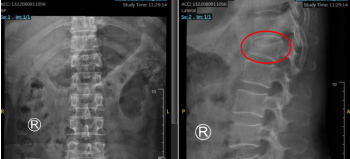

术前X线